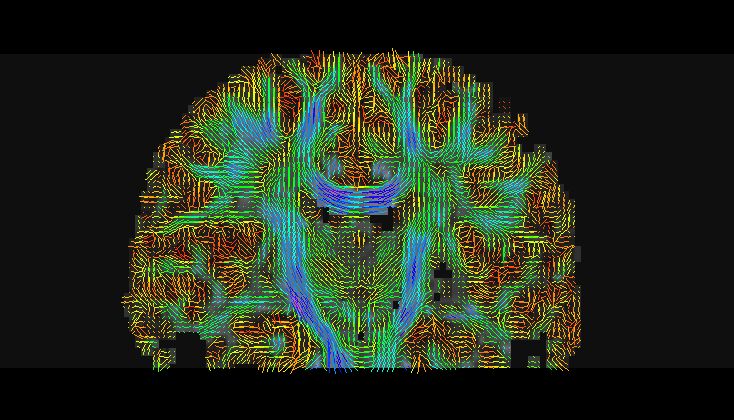

Stochastic Tractography

As a main purpose, the stochastic tractography module helps to evaluate connectivity between two regions of the Grey Matter of the brain. It obviously possible to find from a single region of interest (ROI) specific fiber tracts.